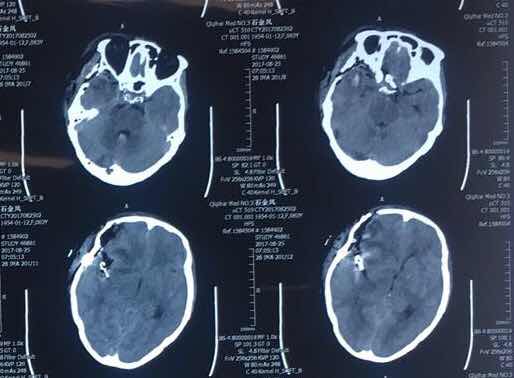

术后头部CT

24日手术紧张而有序的进行,术中证明右侧为责任动脉瘤,与术前判断相符,完美夹闭右侧大脑中动脉瘤后,解剖探查左侧动脉瘤位于左侧大脑前动脉A1段腹侧,指向左侧视神经,一旦误夹可引起视力受损、精神异常等不良后果,最后凭借多年的手术经验及技巧成功将两枚动脉夹闭,第一时间挽救了患者的生命,手术过程顺利,双侧颅内动脉瘤完美夹闭,术后患者清醒,现已下地活动。